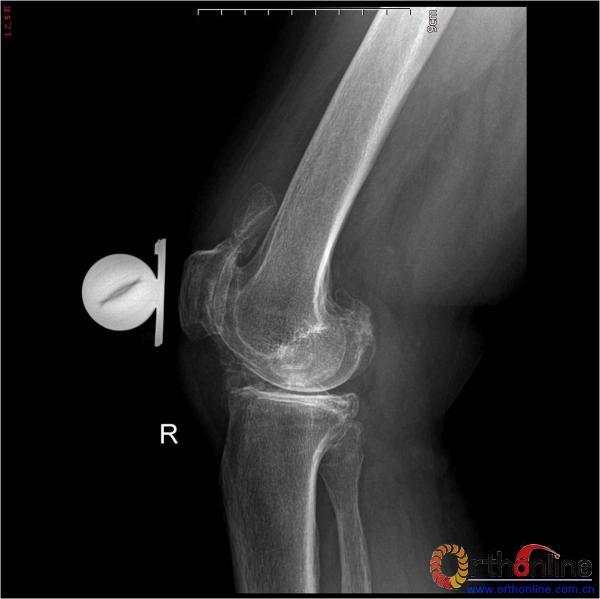

诊断:双膝关节重度骨性关节炎(右侧重)

ROM 右膝10-100°

右膝关节过伸过屈痛(+),压髌、磨髌试验(+),侧方应力试验(-),内侧关节间隙压痛(+)

术前HSS评分 56分

图1、2为术前X片